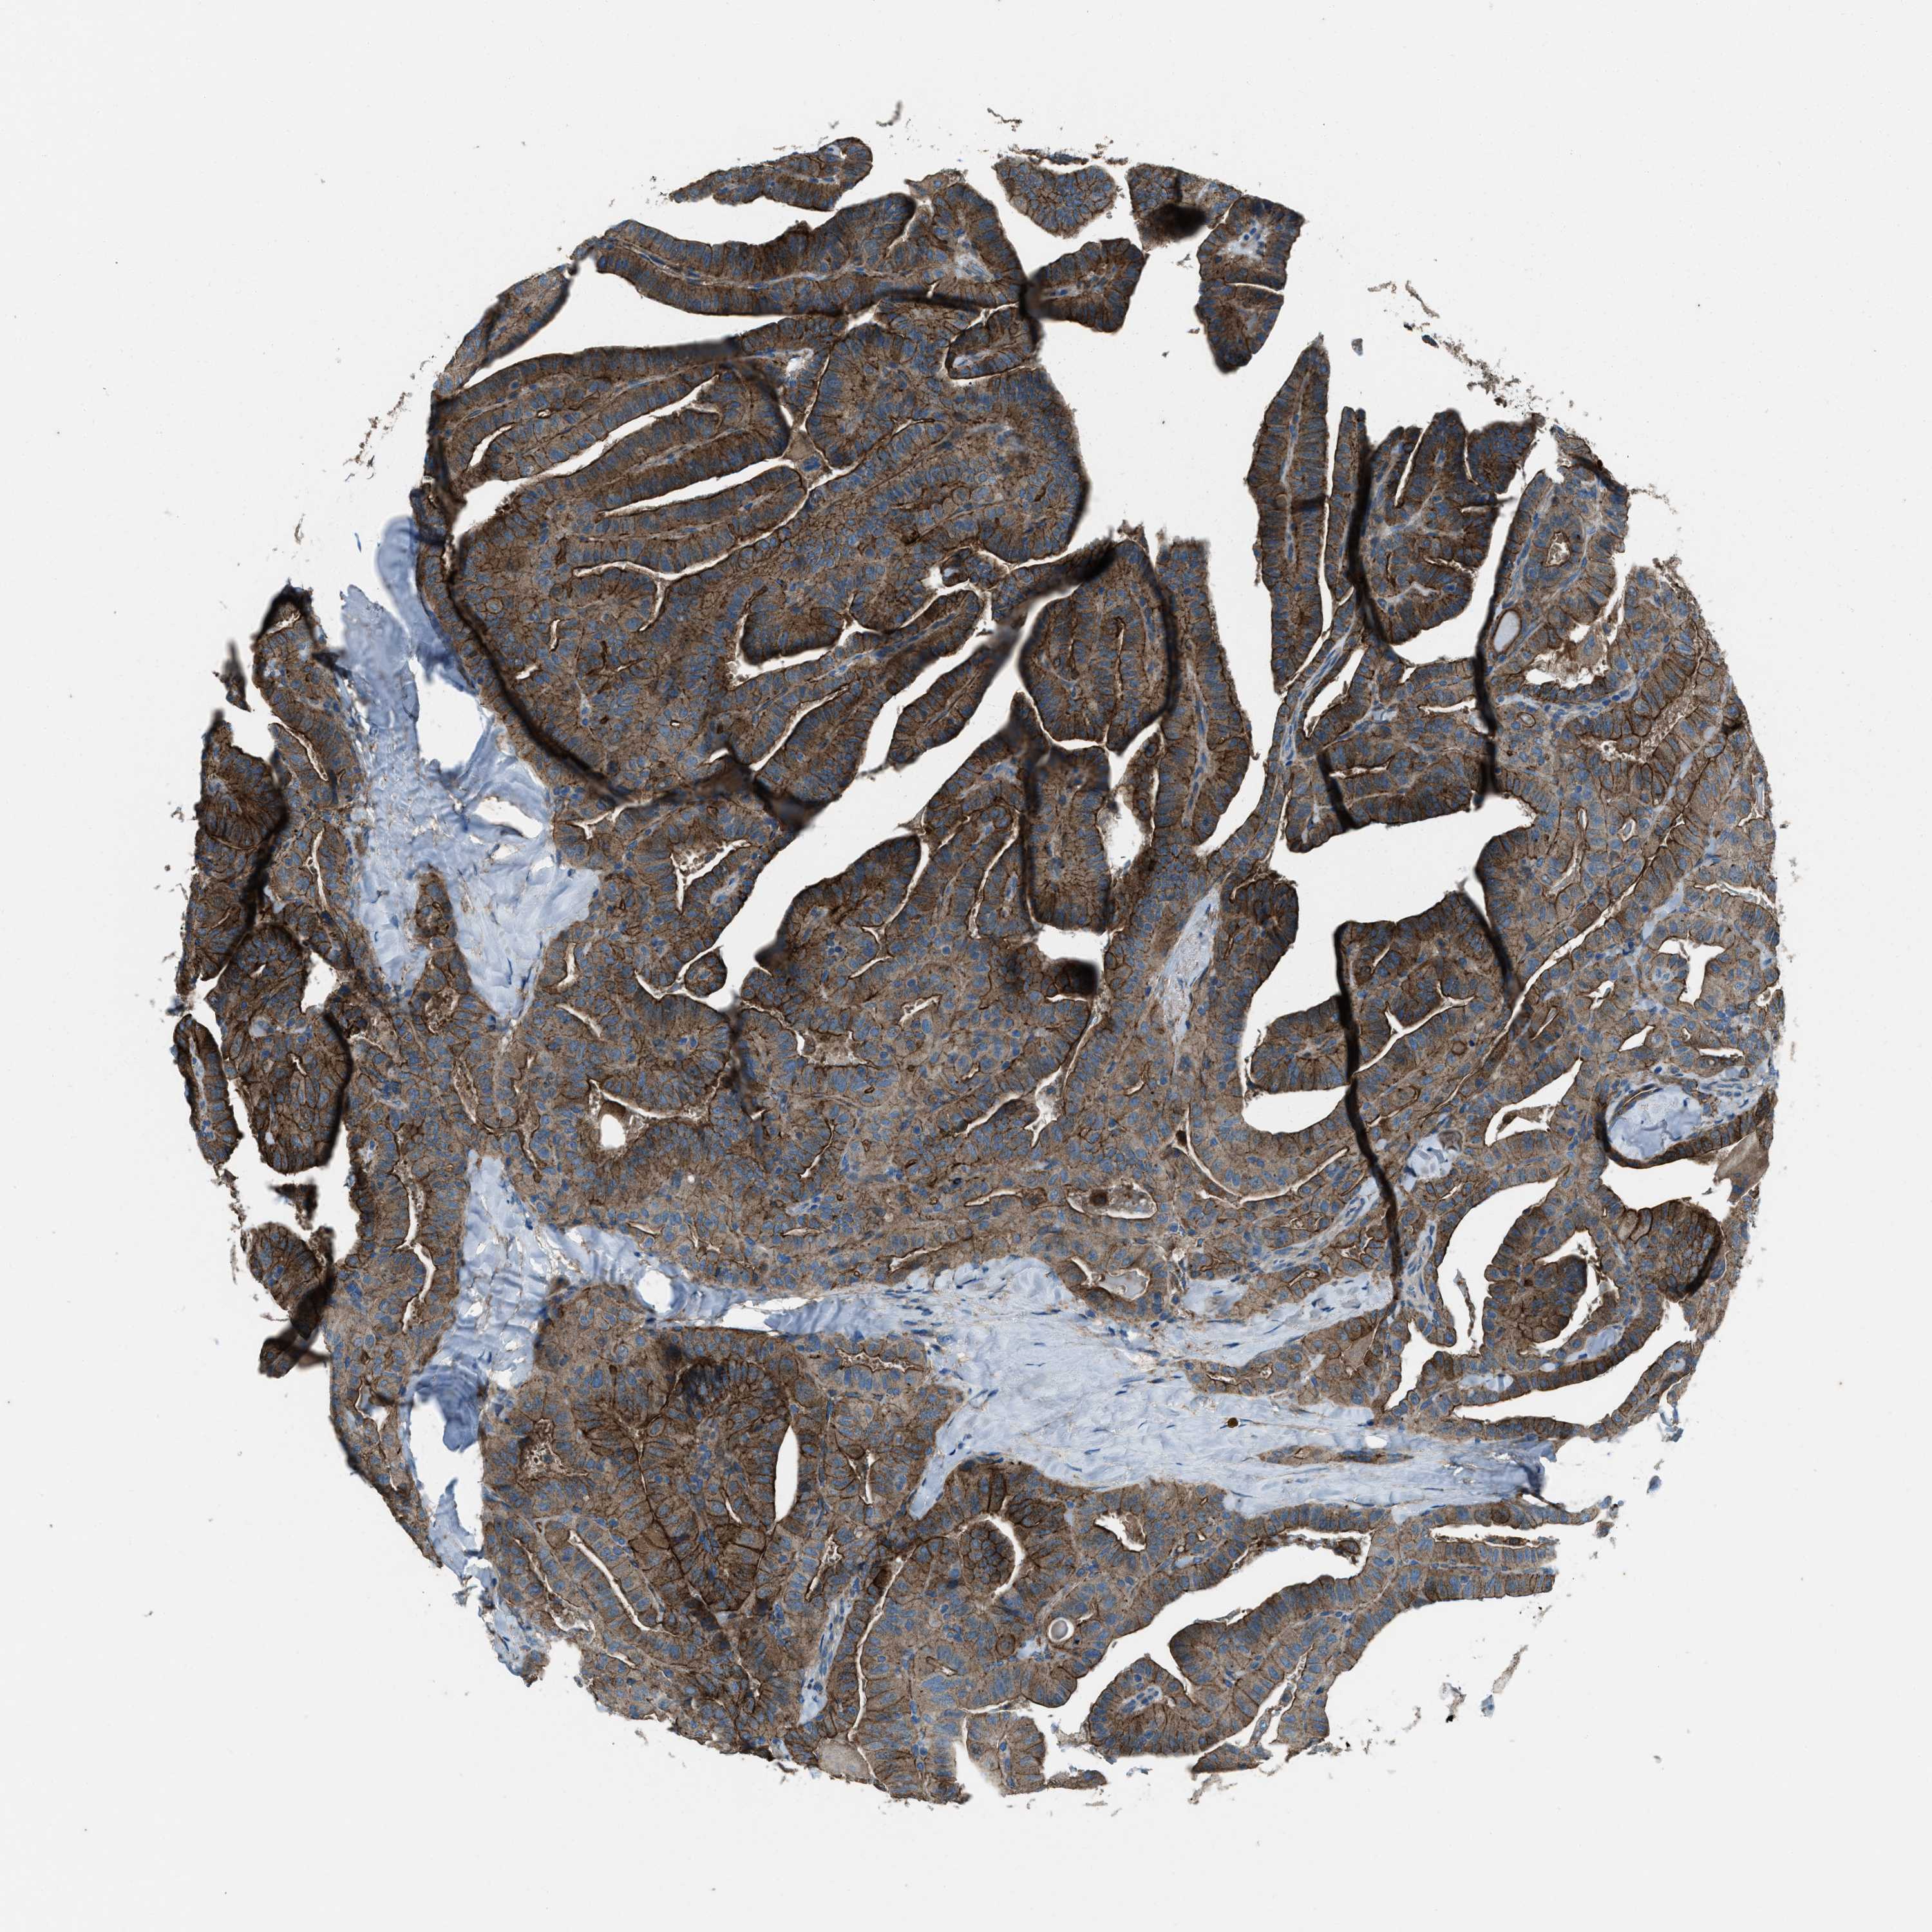

THYROID CANCER - Protein expressioni

A mouse-over function shows sample information and annotation data. Click on an image to view it in a full screen mode. Samples can be filtered based on level of antibody staining by selecting one or several of the following categories: high, medium, low and not detected. The assay and annotation is described here.

Note that samples used for immunohistochemistry by the Human Protein Atlas do not correspond to samples in the TCGA dataset.

Antibody stainingi

Antibody staining in the annotated cell types in the current human tissue is reported as not detected, low, medium, or high, based on conventional immunohistochemistry profiling in selected tissues. This score is based on the combination of the staining intensity and fraction of stained cells.

Each image is clickable and will lead to virtual microscopy that enables deeper exploration of all samples and also displays staining intensity scores, fraction scores and subcellular localization as well as patient and tissue information for each sample.

Antibody HPA020095

Antibody HPA020138

Antibody CAB010878

Antibody CAB080402

Staining

High

Medium

Low

Not detected

Intensity

Strong

Moderate

Weak

Negative

Quantity

>75%

75%-25%

<25%

None

Location

Nuclear

Cytoplasmic/membranous

Cytoplasmic/membranous,nuclear

Papillary adenocarcinoma, NOS

Follicular adenoma carcinoma, NOS